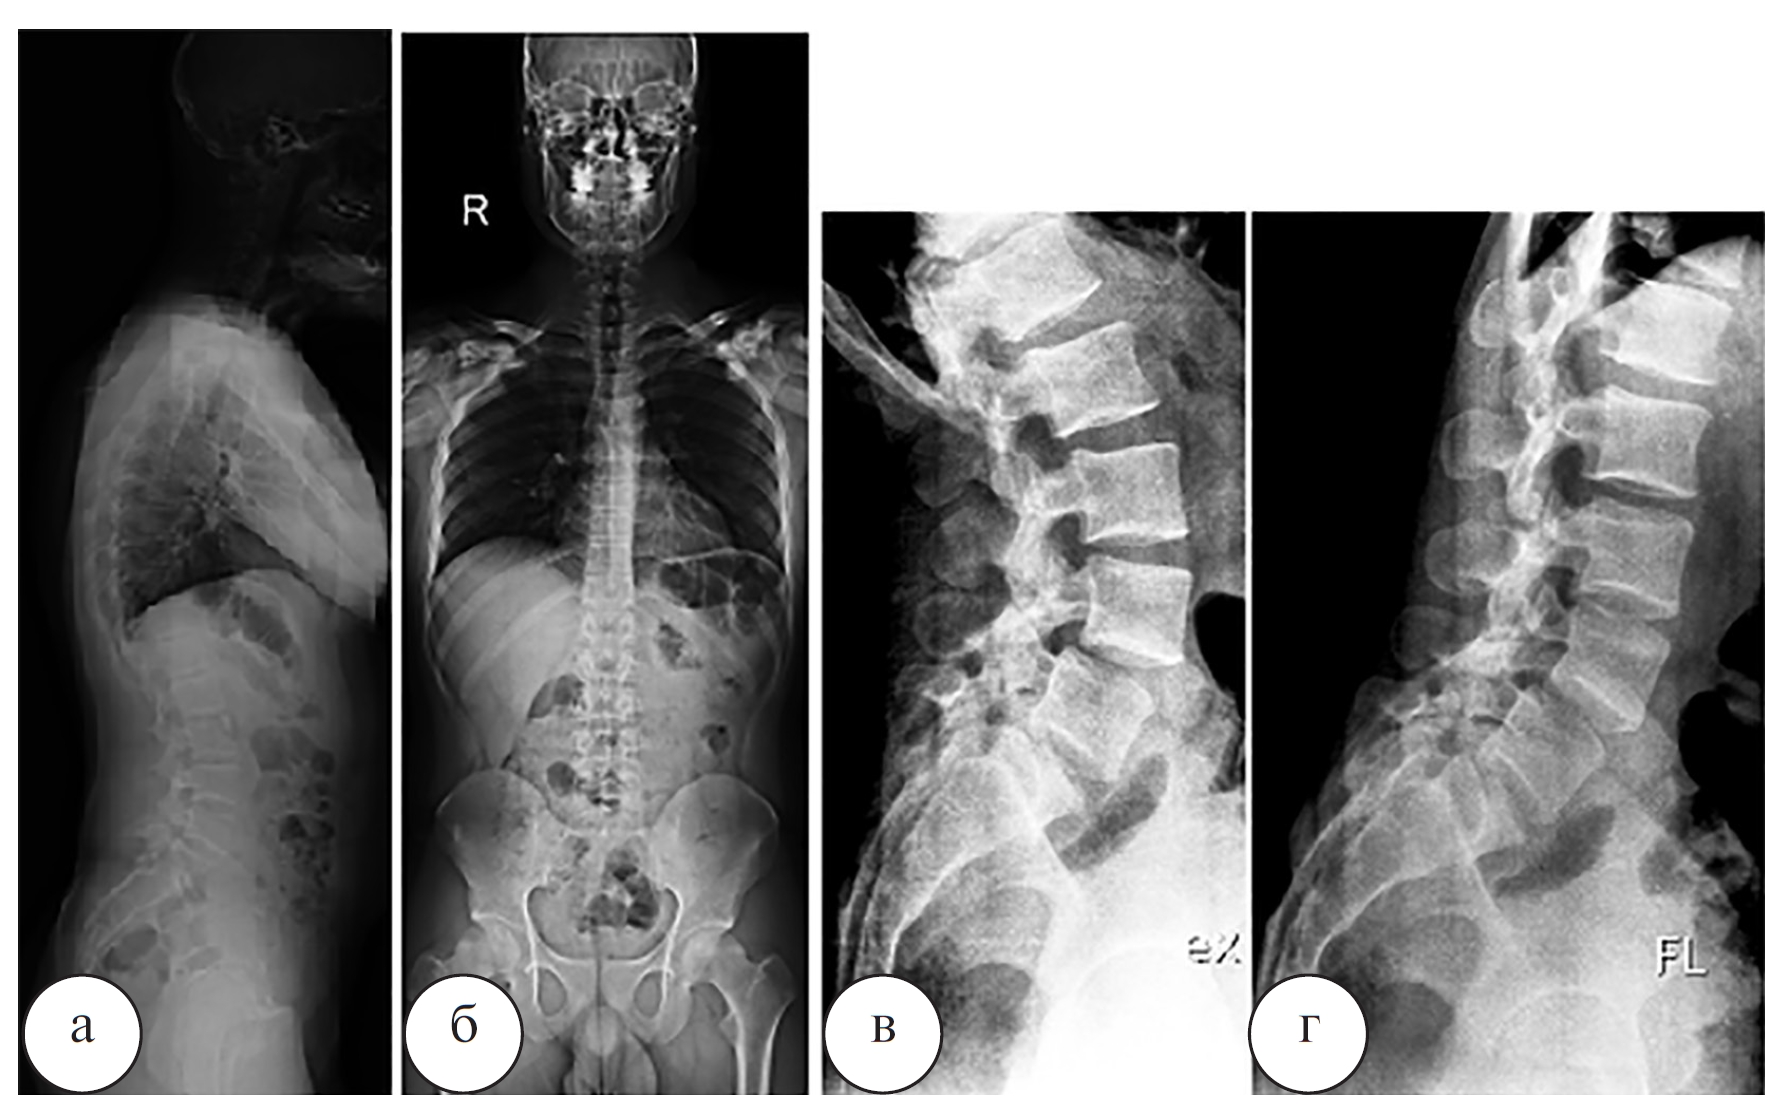

Рис. 5. Телерентгенограмма позвоночника (Full Spine X-Ray, а, б) и функциональные рентгенограммы поясничного отдела позвоночника в боковых проекциях (в, г) пациента Л. до операции

Наблюдение 2. Пациент Л., 19 лет, рядовой контрактной службы. По данным спондилографии, КТ и МРТ позвоночника (рис. 5, 6) был выявлен двусторонний спондилолиз L4, L5 позвонков, минимальный спондилолистез L4 позвонка (I степени). Выполнена операция: костная аутопластика, задний спондилодез дужек четвертого и пятого поясничных позвонков ламинарно-транспедикулярной системой (рис. 7).